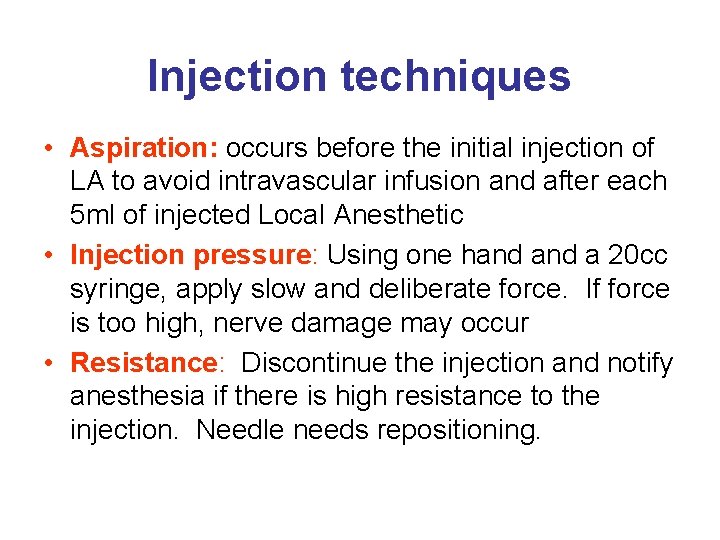

Injection techniques • Aspiration: occurs before the initial injection of LA to avoid intravascular infusion and after each 5 ml of injected Local Anesthetic • Injection pressure: Using one hand a 20 cc syringe, apply slow and deliberate force. If force is too high, nerve damage may occur • Resistance: Discontinue the injection and notify anesthesia if there is high resistance to the injection. Needle needs repositioning.